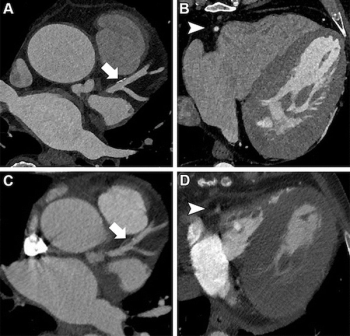

In a study cohort of patients undergoing pre-operative workup for transcatheter aortic valve replacement (TAVR), researchers found the use of photon-counting CT for ultra-high resolution coronary CT angiography had a 96 percent sensitivity rate and an 84 percent specificity rate for the detection of coronary artery disease (CAD).

Photon-counting computed tomography (PCCT) significantly increased the signal-to-noise ratio (SNR) and the contrast-to-noise ratio (CNR) in comparison to dual-source CT (DSCT) at similar radiation dosing, according to a new study of over 100 children with suspected congenital heart defects.